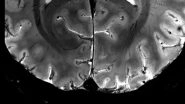

Iseult MRI Scanner: World's Most Powerful MRI Unveiled, Captures Images of Human Brain in Four Minutes; All You Need To Know About Iseult (Watch Video)